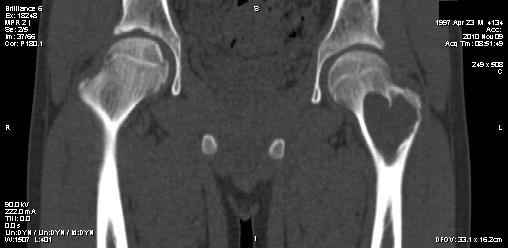

Сергей Тарасов 16 Ноябрь 2010, 15:09

Выполнили, что и запланировали. Обошлись одним крылом. Зафиксировали пластиной. Мысль о возможной фиксации TEN приходила, но... доступны только гвозди Эндера. А ими - не решились.